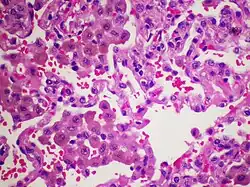

The major hallmark of DIP is the presence of a large number of macrophages within the alveoli that are distributed throughout the pulmonary acini. These macrophages are rich in eosinophilic cytoplasm and frequently include a coarsely granular light-brown pigment. There are usually a few multinucleated large cells. The alveolar architecture is typically intact, however there is a modest chronic inflammatory infiltration inside the interstitium. A moderate quantity of eosinophils might also be present. Lymphoid aggregates can be present.[18]